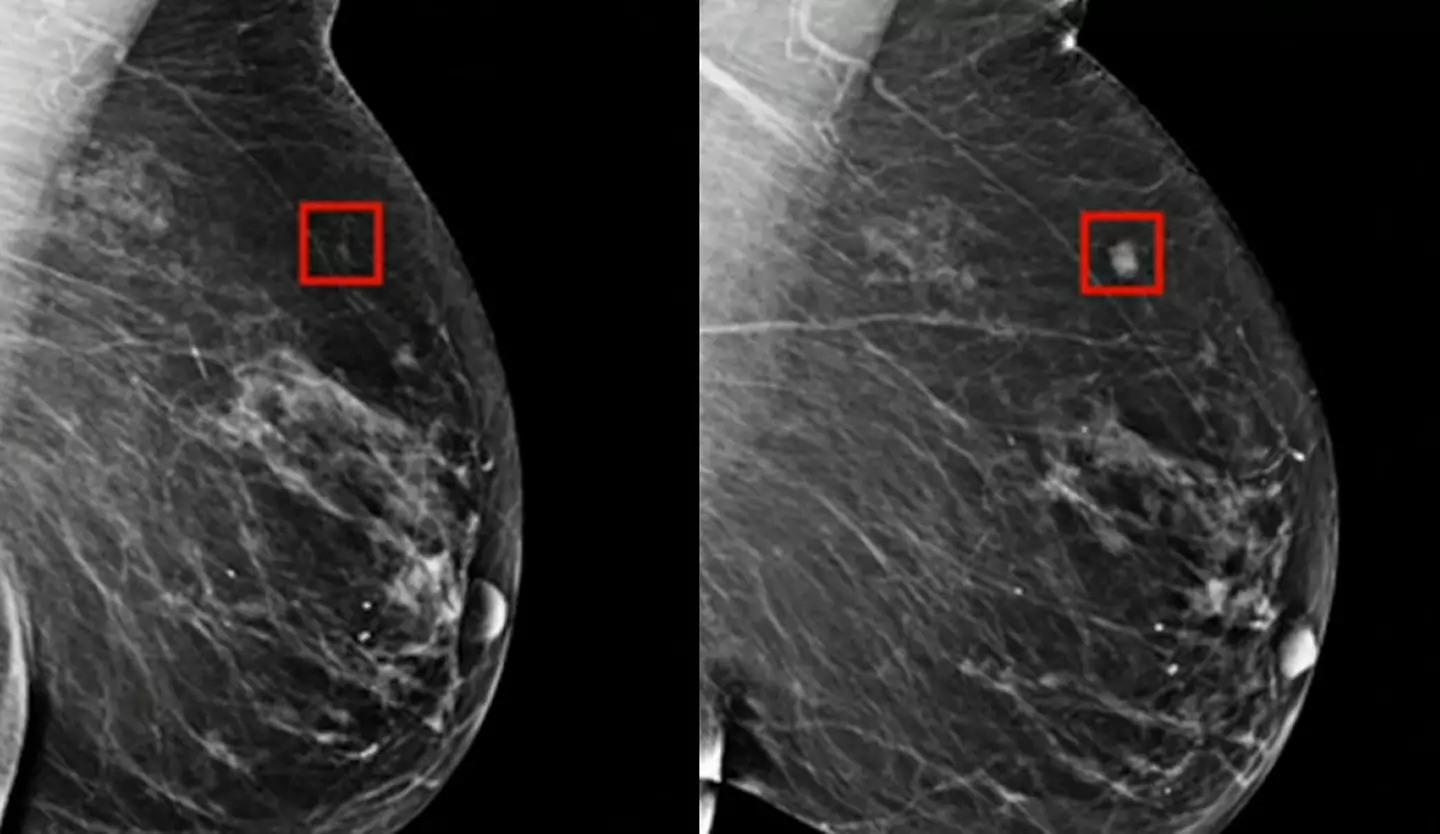

Një program i ‘AI’ zbuloi me sukses kancerin e gjirit tek një grua katër vjet përpara se të zhvillohej. Ndërsa disa përparime të ‘AI’ mund të jenë frikësuese, ato gjithashtu mund të bëjnë një të mirë të konsiderueshme, të tilla si ndihma në diagnostikimin e hershëm të sëmundjeve. ‘AI’ tani po përdoret në shqyrtimin e kancerit për të identifikuar problemet e mundshme shumë kohë përpara se ato të bëhen të dëmshme.

Dr. Larry Norton i Qendrës së Gjirit Lauder shpjegoi për CNN se ‘AI’, e cila ka ekzistuar që nga fundi i viteve 1990, po bëhet më e dobishme në identifikimin e problemeve të mundshme shëndetësore. AI mund të ndihmojë radiologët duke identifikuar zonat në mamografi që kanë nevojë për ekzaminim më të afërt.